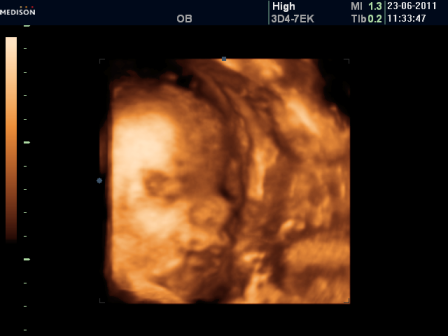

Результаты: УЗИ, КТГ, доплера, скринингаСходили сегодня на крайнее УЗИ) Отпишусь для истории.

Малышик в головном предлежании, БПР 88, ОДЖ 291, ДБ 65,вес примерно 2200!!!)))

Все соответствует сроку 33-34 недели (а у меня щас 32недели)

Сердечко 140 уд.мин.

Плацента по задней стенке матки, степень зрелости 2 (немножко старая,да?), толщина 32мм.

Как всегда,сделали фото и еще записали на диск нашу малявку)Ой,он так прикольно губками чмокает улыбается,прелесть!!!

Прям губки и носик видно даже так четко! :)